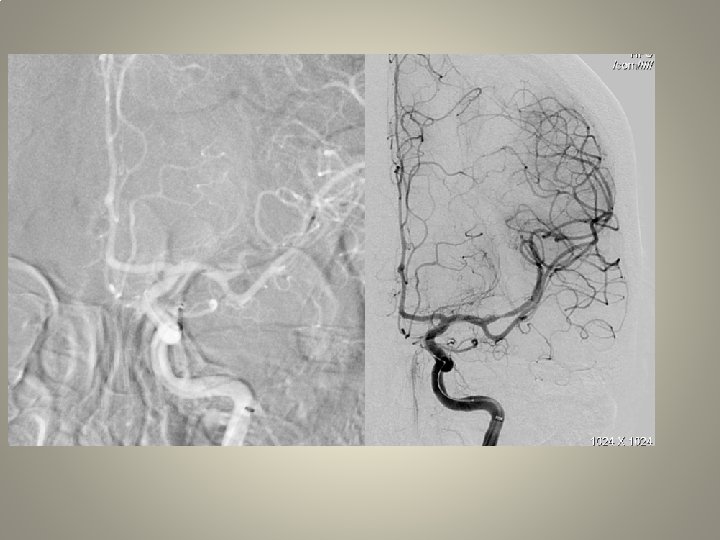

Neden stent? TANDEM lezyon

Neden stent? Distal emboli koruma

Neden stent? Eş zmanlı komplikasyon idaresi